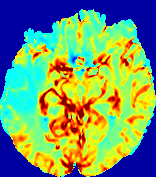

LesionRefer to captionRefer to captionRefer to captionRefer to captionRefer to captionRefer to caption𝐕rgbsubscript𝐕𝑟𝑔𝑏{\bf{V}}_{rgb}Refer to captionRefer to captionRefer to captionRefer to captionRefer to captionRefer to caption𝐕2subscriptnorm𝐕2{\|\bf{V}}\|_{2}Refer to captionRefer to captionRefer to captionRefer to captionRefer to captionRefer to captionRefer to caption3.53.53.52.82.82.82.12.12.11.41.41.40.70.70.70.00.00.0(mm/s)𝑚𝑚𝑠(mm/s)D𝐷DRefer to captionRefer to captionRefer to captionRefer to captionRefer to captionRefer to captionRefer to caption0.0200.0200.0200.0160.0160.0160.0120.0120.0120.0080.0080.0080.0040.0040.0040.0000.0000.000(mm2/s)𝑚superscript𝑚2𝑠(mm^{2}/s)Slice #1Slice #2Slice #3Slice #4Slice #5Slice #6

Figure 4: PIANO feature maps for another patient in the ISLES 2017 training set, where the lesion is located in the right hemisphere. Top row: segmented stroke lesion region (white) on different slices. The corresponding slices for the PIANO feature maps are shown in the following rows.

For a better insight into an estimated velocity field 𝐕𝐕{\bf{V}} and diffusion field 𝐃𝐃{\bf{D}}, we compute the following maps: (1) 𝐕rgbsubscript𝐕𝑟𝑔𝑏{\bf{V}}_{rgb}: Color-coded orientation map of 𝐕=(Vx,Vy,Vz)T𝐕superscriptsuperscript𝑉𝑥superscript𝑉𝑦superscript𝑉𝑧𝑇{\bf{V}}=(V^{x},V^{y},V^{z})^{T}, obtained by normalizing 𝐕𝐕{\bf{V}} to unit length and mapping its 3 components to red, green, blue respectively; (2) 𝐕2subscriptnorm𝐕2\|{\bf{V}}\|_{2}: 222 norm of 𝐕𝐕{\bf{V}}; (3) D𝐷D: scalar field in Eq. 5.

Fig. 3 and Fig. 4 show the PIANO feature maps estimated from two ISLES 2017 patients: all are highly consistent with the lesion in both cases. Details of the blood flow trajectories are revealed in 𝐕rgbsubscript𝐕𝑟𝑔𝑏{\bf{V}}_{rgb} by the ridged patterns and the sharp changes of colors in the unaffected (right) hemisphere, while the flat patterns appearing within the lesion provide little directional information about the velocity and indicate low velocity magnitudes. Velocity magnitudes are more directly visualized via 𝐕2subscriptnorm𝐕2\|{\bf{V}}\|_{2}, from which one can easily locate the lesion where 𝐕2subscriptnorm𝐕2\|{\bf{V}}\|_{2} is low. D𝐷D also indicates lower diffusion values in the lesion, though with less contrast potentially due to the fact that it captures the accumulated effect of CA diffusion at the voxel-level.